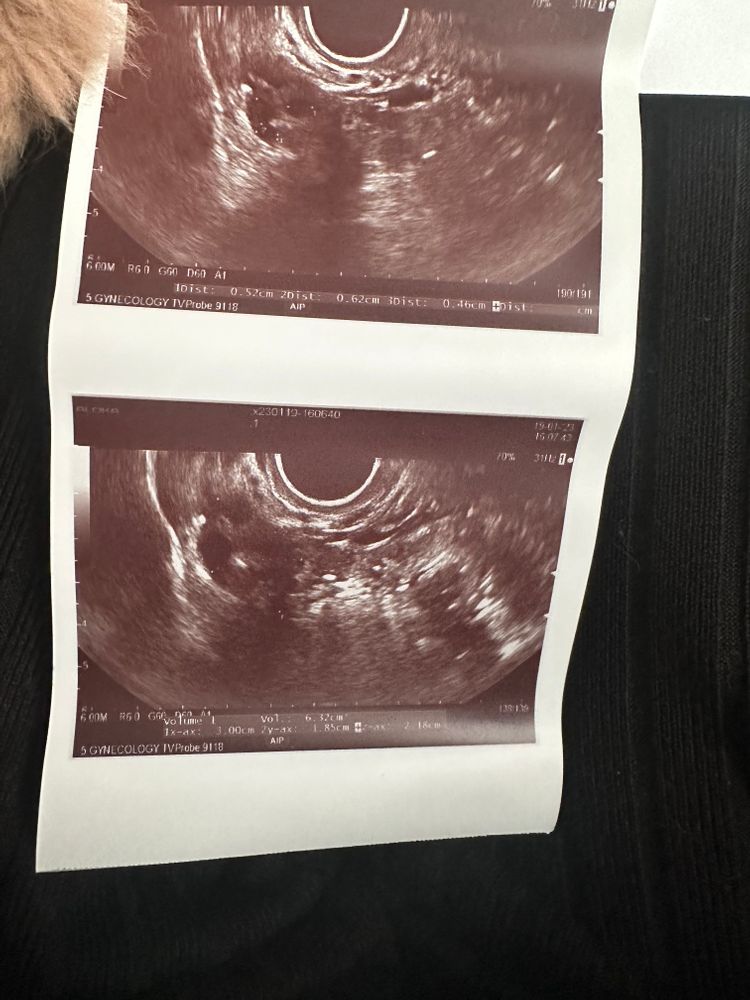

Виктория Виктория в Зачатие 3 года Девочки, оказывается овуляции не произошло…ДФ был, а сегодня его уже нет и желтого тела тоже нет…((( Ждем дня Х (Признаки беременности / Тесты) Посмотрите еще 20 записей на эту тему Отменить Ответить Вероника Так может у вас позже будет ещё овуляция в этом цикле,там вон фолликул 10мм почти… 19.01.2023 Ответить Зима А хгч почему вырос не сказали ? 19.01.2023 Ответить Жду результат 8 дпо Ближе к вечеру тянет немного живот,грудь не болит но тяжелая Чаты Беременных Выберите чат: Январята-2026 Февралята-2026 Мартята-2026 Апрелята-2026 Майчата-2026 Июнята-2026 Июлята-2026 Августята-2026